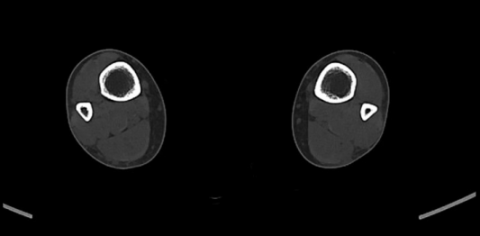

Image CT axiale.png

Image CT axiale montrant un épaississement cortical, plus marqué à droite.